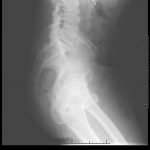

Significant findings:

The AP and lateral pelvis x-rays revealed two sewing needles, 60 mm in length, within the soft tissue over the anterior right lower hemipelvis. In addition, the AP view showed emphysema involving the right hemiscrotum (arrow), concerning for perforated bowel.

In this case, the patient attempted to drain the suspected abscess with a needle, resulting in bowel perforation. The sensitivity for plain abdominal radiographs to detect needles in the peritoneal cavity varies by needle size. In a study of retained surgical needles, radiographs had a sensitivity of 99% for needle size greater than 25 mm.4 Although plain radiographs are not as sensitive as multi-detector computed tomography in the detection of free air, a recent retrospective study showed a sensitivity of 80.4%. The study was limited in that only 8.8% of perforations involved the small bowel or colon.5 Due to free air seen on x-ray, the patient was taken to the operating room where a cecal perforation was noted in addition to the incarcerated inguinal hernia.